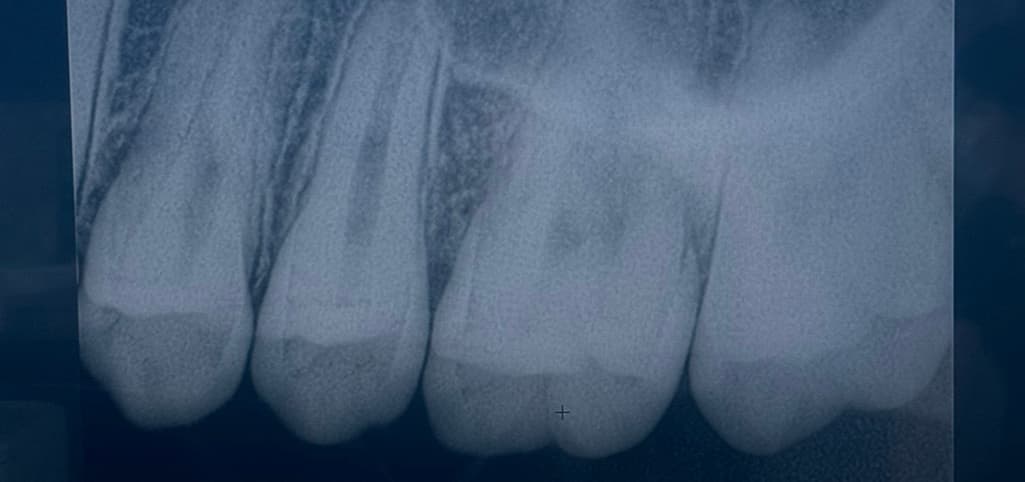

25~26 치아고 첫번째, 세번째 사진이 최근 두번째 사진이 올해 2월 입니다 인접면 충치가 맞는지 얼마나 진행되었는지 궁금합니다

엑스레이 상에서 명확히 관찰되지는 않는 것으로 보이며 관리 하면서 지켜봐도 될 것 같습니다.

엑스레이 상으로는 인접면 충치가 심해 보이진 않으니 일단은 관리를 해서 사용해보셔도 될것같습니다.

25~26 치아고 첫번째, 세번째 사진이 최근 두번째 사진이 올해 2월 입니다 인접면 충치가 맞는지 얼마나 진행되었는지 궁금합니다 -> 25,26 사이 인접면 충치 크게 문제 없어 보입니다

사진으로 봤을 경우에는 인접면에 어두운 면이 보입니다. 충칠 가능성이 높지만 정확한 확인은 육안으로 확인을 해봐야 알 수 있을것으로 생각됩니다.

자세한 확인을 위해서 치과에서 진료를 받아보는 것을 권유드립니다.